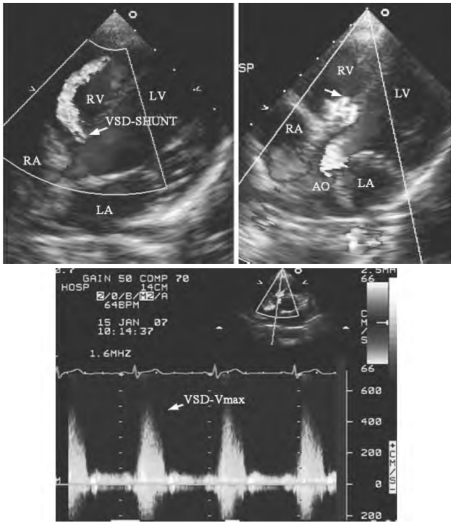

1.20.2二、室间隔缺损